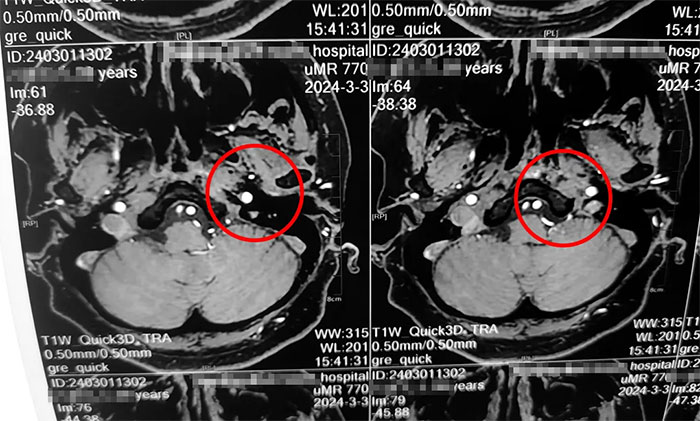

杨忠旭教授详细了解了刘阿姨的症状、病史资料、影像资料等。杨忠旭教授分析指出,传统的三叉神经痛大多发生于面部,而刘阿姨疼痛的部位为舌头,和最普遍的三叉神经痛位置大相径庭,但其实支配舌前2/3的感觉的舌神经,也是自三叉神经发出,所以此处的疼痛完全符合三叉神经痛的表现。结合影像资料,杨忠旭教授指出患者左侧三叉神经根部与临近小血管关系密切,手术指征明显,未见明显手术禁忌症。

▲ 左侧三叉神经与临近小血管关系密切